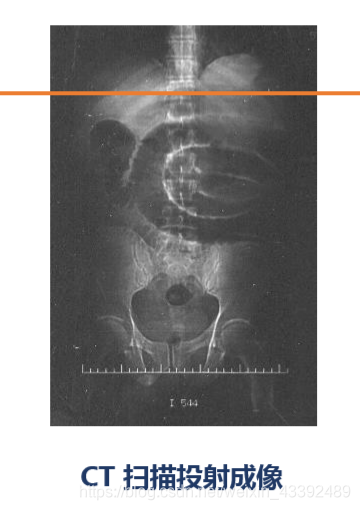

CT (Computed Tomography) 计算机断层摄影术